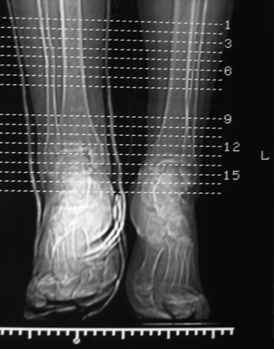

Все коллеги как-то враз заговорили об остеопорозе. Неужели поставили диагноз по снимкам ЧЕРЕЗ ГИПС? Не рискну. Так что диагноз остеопороза - не факт, а лишь предположение, основанное только на 62-летнем возрасте. Этого мало.

Снимков через гипс, увы, недостаточно и для ответа на вопрос Ю.А.Булахтина. Рентгенограммы - в студию!

Посмотрели снимки после репозиции - не понравилась зона синдесмоза.

Сделали 3/4-е - впечатление, что в 99-том там что-то было. На

5.11.09г. запланирована КТ.